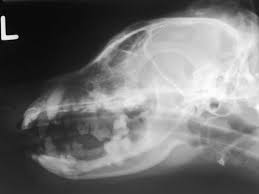

Brain Tumors In Cats Petmd from www.petmd.com In the sections below, we look at several types of brain tumor and their specific symptoms however, signs that a headache could be a symptom of a brain tumor include: A tumor forms when cells divide abnormally and rapidly. Brain tumours in dogs and cats are unfortunately as common as they are in people. Since there's limited space within the skull, signs and symptoms of a brain tumor typically develop when abnormal tissue expands and destroys or pushes on healthy brain tissue, the tissue around the. Symptoms may arise because of impairment tumors in the upper regions of the brain may also affect the brainstem if they cause pressure resulting in brain tissue herniating (getting pushed). This allows doctors to see inside the body without cutting it open and the procedures is commonly used to find problems inside the skull, such as brain tumors or signs of a stroke. Overall, seizures are a more common sign of a brain tumor in dogs, while behavior change is more common in cats. After taking note of clinical signs and conducting basic blood work, your vet performs an ultrasound or magnetic resonance imaging on your cat's head to diagnose a brain.

A brief guide ÿ part of the educational pet disease series from lap of love. It is usually thought to be a symptom of a tumor in the cerebellum. Surgery using magnetic resonance imaging (mri): However, treatment may help to reduce some of the signs seen in a patient with a brain tumour. Anybody can develop a brain tumour but research has shown that there are factors that can increase the chances of developing one. Find out what to watch for. A brain tumor expert shares seven brain tumor symptoms to watch out for and advises on the best type of place to seek brain tumor treatment. Brain tumors cause signs by compressing or invading the brain. Brain tumours in dogs and cats are unfortunately as common as they are in people. Brain tumors are a common cause of neurological dysfunction in older dogs and cats. For many people with a brain tumor, they were diagnosed when they went to the doctor after experiencing a problem. The resulting signs relate directly to the area of the brain affected and are not specific whenever a dog or cat that is greater than five or six years of age has a new onset of seizures, a brain tumor is a possible differential and ruled out by. Persistent headaches, particularly if the person has no history of.